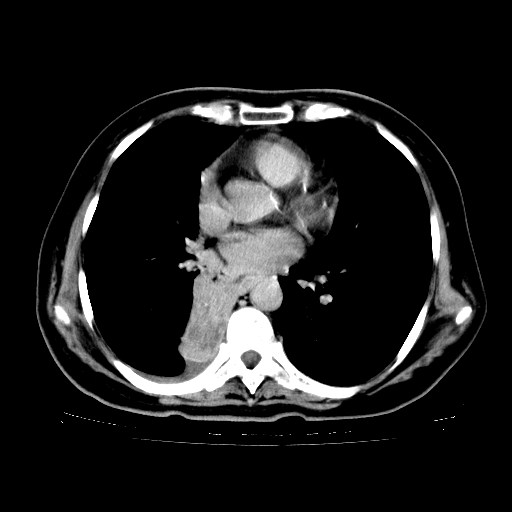

女,70岁,咳嗽、咳痰一个月,低热一周。

1.左上肺结核,部分纤维化。右肺中下叶部分肺不张,内见液化、坏死及点状钙化,右中下叶支气管壁增厚、管腔狭窄,见多个点状钙化,结合临床考虑支气管内膜结核,建议痰检查抗酸杆菌并参考血沉。两肺多个小圆点状高密度灶,境界模糊,多考虑结核肺内播散。但本人年龄较大首先应支气管镜检以除外右肺癌。

2.胸主动脉夹层。

支持,首先一元论解释。胸主动脉部分层面环形低密度,中心强化。环形影不强化。不象真假腔的改变。我考虑动脉炎,不太支持夹层动脉瘤-和大家的观点不一致,希望楼主让患者再做个心血管的彩超吧。